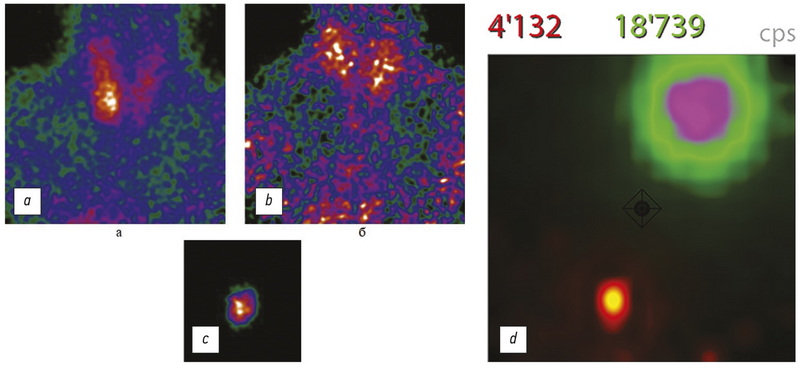

术中成像的方法中,超声波是最常用的,它可以实时获取有关感兴趣区域的信息。 然而,随着技术的发展,除了超声波之外,还可以使用多通道伽马探头,其中包括便携式(Sentinella-102)和手持式(CrystalCam)伽马相机(图6)。

图 6。使用多通道伽马探测器 Sentiella-102 (a – c) 和 CrystalCam (d) 获得的图像。

这些设备的操作基于相同的物理原理,但它们实现了不同的技术方案,这使得手持伽马相机的使用成为更有前景的发展方向(表 3)。 由于其更好的特性,CrystalCam 提供了比 Sentiella-102 更高质量(对比度)的图像。